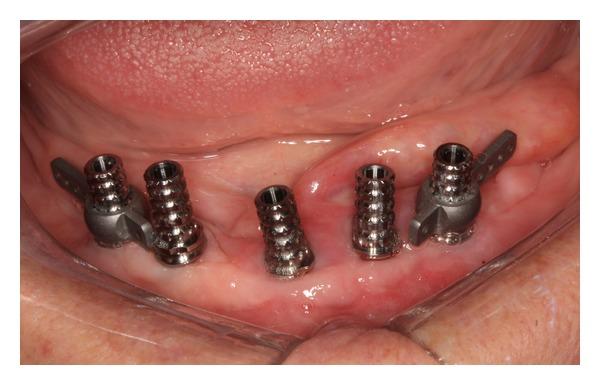

In mandibular edentulous patients, treatment based on immediate loading with rigid splinting in the mandible is well accepted; however, it is cost and time dependent, which sometimes limits this type of rehabilitation. To overcome these problems, the technique of immediate loading using a semirigid splinting extension system has been developed. Its advantages include low cost, technical feasibility, and reduced clinic time. This clinical report presents the applicability and the predictability of semirigid splinting of implants in the mandibular arch of an edentulous patient using a distal extension bar prosthesis system.

在下颌无牙患者中,基于下颌即刻负重并采用刚性夹板固定的治疗方法已被广泛接受;然而,这种方法成本较高且耗时,有时会限制此类修复方式的应用。为克服这些问题,已开发出使用半刚性夹板延伸系统进行即刻负重的技术。其优点包括成本低、技术可行性高以及临床时间缩短。本临床报告介绍了在一名无牙患者的下颌弓中使用远端延伸杆假体系统对种植体进行半刚性夹板固定的适用性和可预测性。